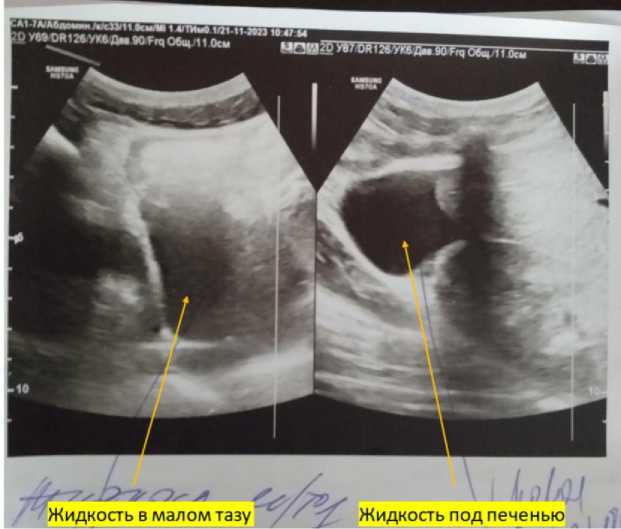

УЗИ органов брюшной полости 21.11.2023 г. 10 ч 47 м на аппарате Samsung HS70A конвекс-ным датчиком частотой 1–7 мгц: у правой доли печени жидкость 3,4 см; поджелудочная железа: головка – 26,7 мм, тело – 15,7 мм, хвост – 26,7 мм, однородность–неоднородная за счет мелкоочаговых диффузных изменений; в малом тазу жидкость до 7 см (рис. 2).

Рис. 2 . Жидкость в области правой доли печени и в малом тазу